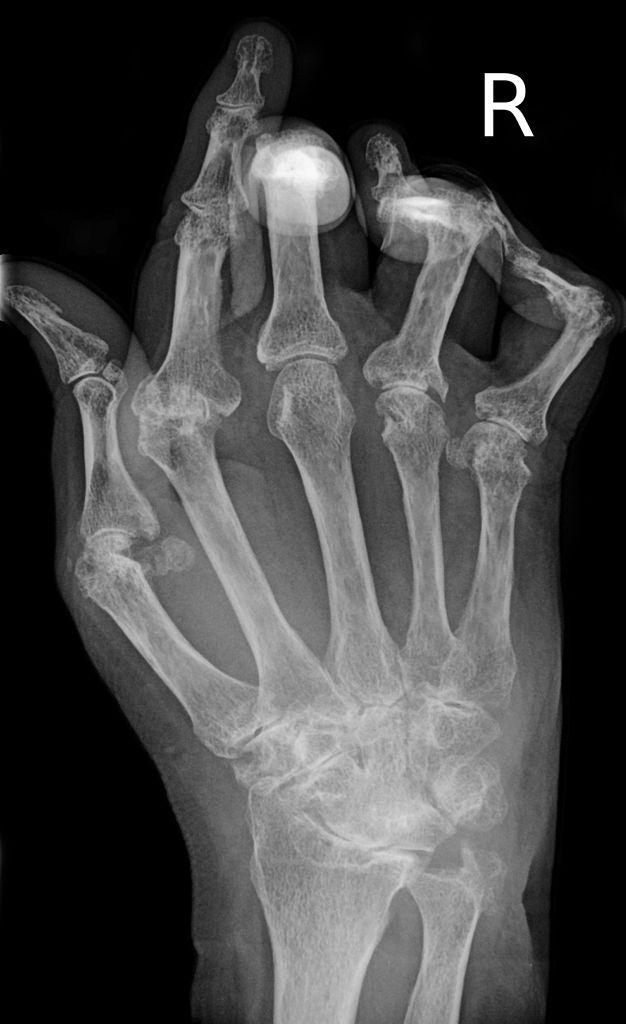

; La palabra Artritis proviene del griego articulación e inflamación; que se traduce como la; duelen mucho, de repente se hinchan y si se toca la zona sientes la parte muy caliente; luego cuesta mover la zona y si de seguir el efecto siguiente es una deformación.

La artritis podemos decir que en efecto es por lo general y agrupa a todas las enfermedades que tengan que ver con la inflamación de esta parte del cuerpo; por ejemplo la Artritis Reumatoide que es una de las mas comunes; pero no la única ya que existen muchas mas calegorizadas de acuerdo a su nivel de efecto.

; La Artritis Reumatoide es una enfermedad Crónica y Degenerativa que se caracteriza por provocar la inflamación de la membrana sinoval; esta membrana es la que alimenta, cubre y proteje los cartílagos de las articulaciones.

¿Qué es la Artritis Reumatoide? La artritis reumatoide es una enfermedad con carácter autoinmune que provoca un incremento del líquido sinovial en las articulaciones, lo que provoca inflamación y deformación de estas. Estos síntomas producen dolor y limitación de movimiento. Es una dolencia evolutiva, es decir, empeora con el tiempo. Afecta principalmente a las articulaciones de las manos y muñeca ...